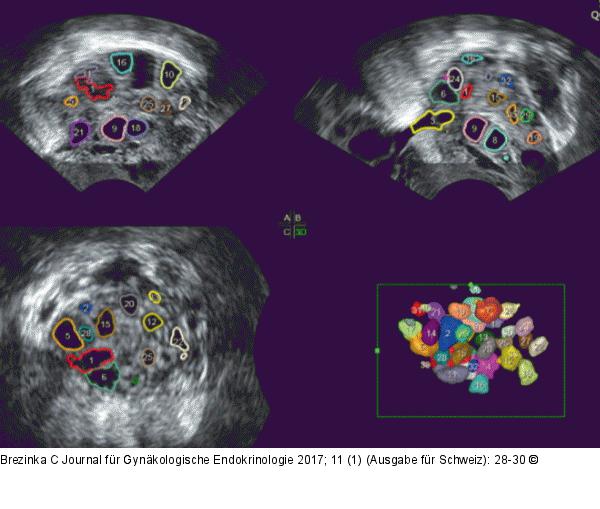

Abbildung 1: Sono-AVC™-Methode Mit der Sono-AVC™-Methode können auch winzige flüssigkeitsgefüllte Räume im Ovar erfasst werden. |

Mit der Sono-AVC™-Methode können auch winzige flüssigkeitsgefüllte Räume im Ovar erfasst werden. |